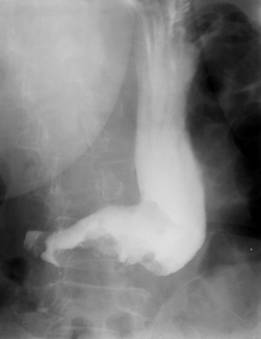

Grande ulcer de

estomac au grand coubure ( portion horizontale ) |

Niche Hausdeck de ulcere de la

petit courbure . Situe a inferieure du cardia . |

Image en etoile de grande

niche de la petit coubure avec image de

convergence des plies muqueuse saint vers la lesion

. |

Niche en aspect

doigtier de la petit courbure . Image TOGD de estoma

en OPD |

Ulcere de estomac prepilorique . Une

deformation antrale . |